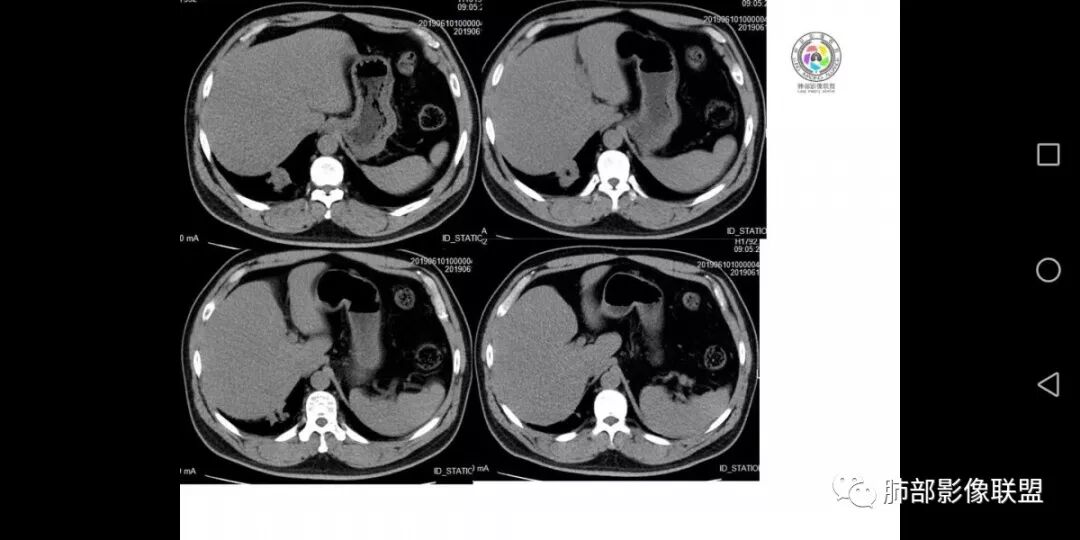

患者男,45岁,因乏力、低热、心悸入院,最高体温38℃,偶有咳嗽、无咳痰、咯血,肿瘤标志物阴性。

影像资料

右肺下叶结节,边界清,周围有胸膜牵拉,内部见坏死,低热,考虑结核。

右肺下叶后基底段结节边缘收缩平直 ,局部膨隆  ,延迟强化,内见坏死,考虑炎性肉芽肿。

右肺下叶后基底段胸膜下肿块,边缘平直、凹陷为主, 局部膨隆 ,周围模糊毛玻璃影及锁条, 内见坏死,明显强化,较均匀,下缘糊墙,考虑炎性,慢性脓肿?鉴别炎性合并肿瘤。

中年男性,乏力  低热入院,胸CT:右肺下叶后基底段结节样病变,病灶周围可见细支气管扩张,病灶边缘可见短软毛刺,病灶周围有毛玻璃影,冠状位肺窗病灶与膈胸膜呈宽基地,纵隔窗可见病灶内空洞及低密度区,增强明显强化及延迟强化,考虑良性感染性病变,隐球菌肺炎?,结核?。但在冠状位肺窗有一支细支气管在病灶旁有截断,还得除外肺癌的可能性。

中年男性,低热,咳嗽,偶有咳痰,右肺下叶可见一不规则结节影,边缘有收缩,有膨隆,周边可见磨玻璃影,可见分叶,延迟强化,内有坏死,似有颗粒感,空泡,胸膜有牵拉,倾向于腺癌,鉴别炎性病变。

患者主要表现低热,乏力,伴少量咳嗽等症状,右肺后基底段不规则肿块影,有"平直,刀切征",局部有膨隆,周围模糊,有晕征,分叶,有细软毛刺,部分胸膜牵拉,中间有低密度坏死,有空泡,延迟强化,良性征象稍偏多点,考虑隐球菌?需排除周围性腺癌,淋巴瘤。

男,45岁;乏力、低热、心悸,38°,偶咳;症状像结核,但无钙化,无积液;三期:35-57-71偏心空洞,冠状位胸膜有牵拉力:需考虑鳞癌,男性,45岁,年龄偏小,吸烟史?

不均匀强化,三期强化形式是否符合鳞癌,渐进性强化?结核:空洞,渐进性强化,段样分布,但没有卫星灶;

处置:结核相关检查,仔细观察与支气管关系,按我的习惯,多b值观察细胞密集程度。

中年男性,右下肺叶后基底段结节影,周围有晕,边缘软毛刺,收缩力弱,边缘平直凹陷,支气管进去后截断,长轴与胸膜平行,中心有坏死,延迟强化,考虑炎性病变,隐球。

中年男性,乏力,低热,右肺下叶后基底段近膈肌缘小团块样病灶,边缘平直,部分内凹,周围磨玻璃,边缘模糊不清,周围少许毛刺,柔软,增强后明显渐进性强化,其内可见少许低密度区,边界清晰,考虑感染性病变,op合并坏死可能。

右下叶病灶,周围ggo边界清,轴位病灶似乎有收缩,平直征,但是冠状重建可以看看病灶边缘膨隆,强化不均匀,持续强化,结合病史首先考虑肺癌,腺癌可能性大,鉴别隐球,op。

患者中年男性,以乏力、低热、心悸入院。胸部CT:右肺下叶后基底段近胸膜实性结节灶,病灶周围磨玻璃模糊影,可见短毛刺,边缘呈刀切、平直,冠状位肺窗病灶与膈胸膜呈宽基地,纵隔窗可见病灶内空洞及低密度区,增强明显强化及延迟强化,综合考虑良性感染性病变。肺隐球菌病可能大,机化性肺炎、腺癌次之,结核待排。

中年男性,低热乏力入院,右肺下叶后基底段结节影,边缘收缩平直,周围有晕,有细软毛刺,内有低密度坏死,明显强化。有胸膜牵拉,考虑感染性病变:op?隐球菌肺炎?肺结核?鉴别肺癌!

中年男性,以低热、乏力为主要症状,右下叶近胸膜病灶,支气管进入但有近端堵塞,周围有短毛刺,磨玻璃影边界不清,周边有条索状纤维灶,病灶有强化和点状坏死,考虑炎性肉芽肿可能性大,隐球?目前整体考虑炎性,但具体是啥是猜的。

右肺下叶后基底段结节,边缘较清,有浅分叶,病灶长轴与胸膜平形,以平直收缩为主,局部稍膨隆,有长短不一的毛刺,边缘模糊,周围有小片状模糊hggo,中心有小空泡或小空 洞,内壁光整,增强后延迟强化,提示会不会有纤维组织成份,而且空腔内壁强化明显且完整,邻近胸膜有糊墙,考虑炎性病变,机化性肺炎合并脓肿?鉴别癌。